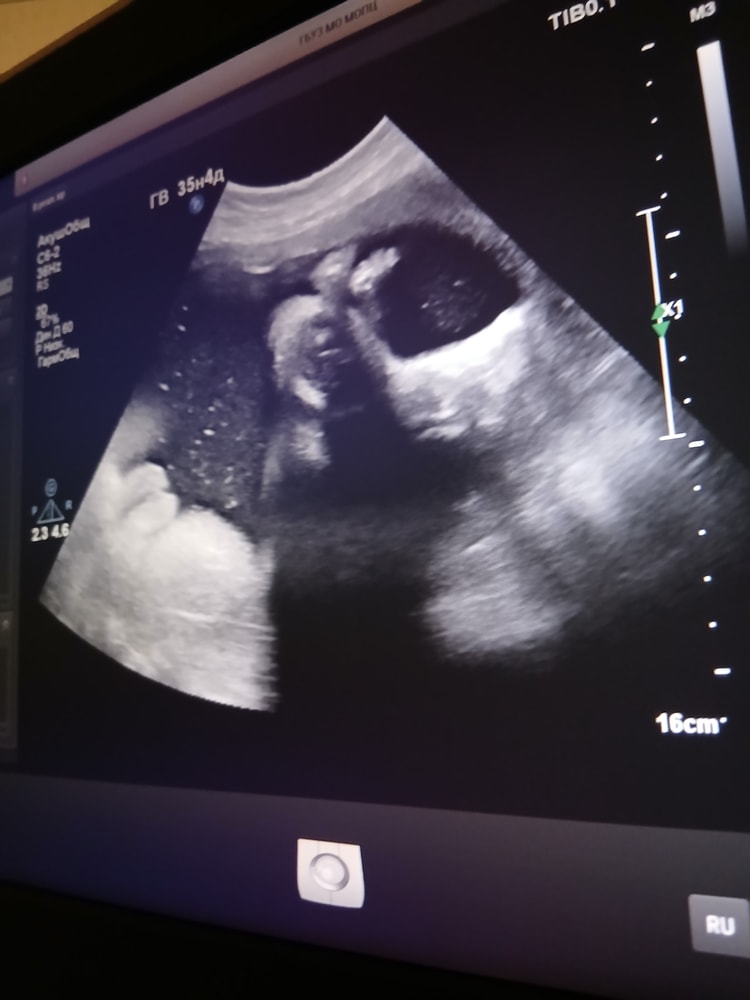

Вот мой мальчик) 100% мальчик, завтра 5 месяцев. Я тоже была уверена, что во мне дочь)

Анюта Долгополова,

примерно так и выглядит,только не такой пухлый на более раннем сроке😁

Левый нижний угол)